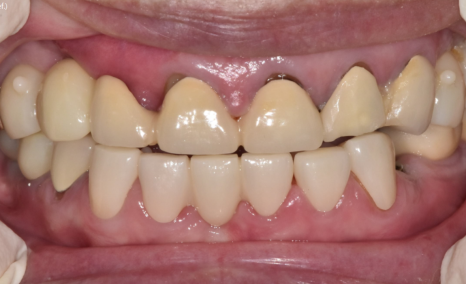

결과적으로,

아래 앞니 7개는 크라운으로 살리고,

총 12대의 임플란트를 더 식립하여

임플란트 보철로 수직 고경을 다시 세우는 방식으로

전체 교합을 재구성했습니다.

치료가 마무리된 뒤

환자분은 거울을 보시더니

“전에는 입이 쏙 들어가 보였는데

이제는 괜찮아 보여요”

라며 환하게 웃으셨습니다.

230211 (전) 240510 (후)